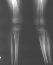

X-ray Set 2. 16 Months post Fracture, Right 8* Left 26* Mechanical axis, Left 34* Femoral Tibial Angle.

At this time the child was experiencing significant pain and inability to ambulate. He was treated with varus producing closing wedge osteotomy of the proximal tibia with neutral alignment